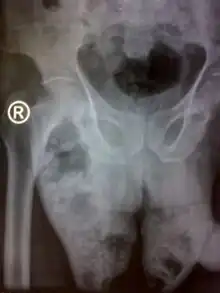

Laboratory tests and medical imaging may support the diagnosis, determine severity, and predict outcomes.[4] X-rays and ultrasound may show the presence of gas below the surface of the skin.[4] A CT scan can be useful in determining the site of origin and extent of spread.[4]